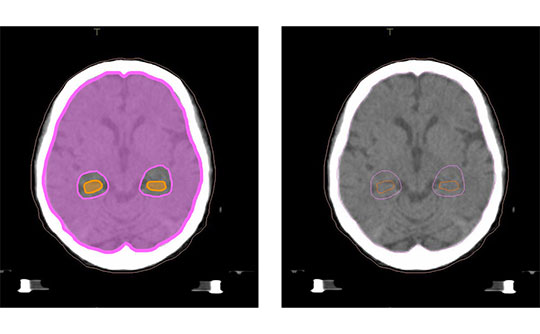

脳を上から輪切りに見た図

左:放射線を当てる範囲(ピンク)と記憶に関わる海馬(オレンジ)を示した図

右:脳の画像(比較用)

記憶への影響を減らすため、海馬を避けて放射線を当てる方法です。